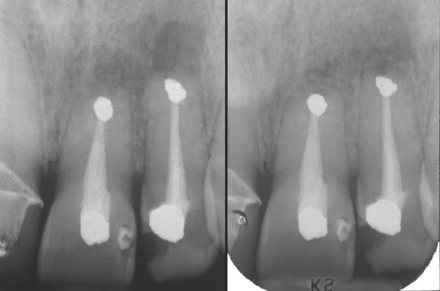

Radiographic examination

Radiographs demonstrate both anatomical and pathological features at the apex of the tooth (Fig. 6.4). A radiograph may demonstrate an incompletely sealed root canal, or bone loss around the apex of the tooth involved. If there is chronic apical disease, a lesion with the physical characteristics of a cyst may be identified at the apex of the tooth. Rarely, the cause of a failed root filling cannot be established through clinical or radiographic examination but it may become apparent when surgical endodontics is undertaken. For example, a root fracture not detectable clinically or radiographically may be identified on surgical exploration.

image

Fig. 6.4 Preoperative radiograph of upper left central and lateral incisors before surgical endodontics.

The operator should also consider the position of the apex of the tooth in a mesiodistal direction. If the apex of the tooth to be treated is inclined towards an adjacent tooth root, there is a risk of damaging the adjacent root structure.